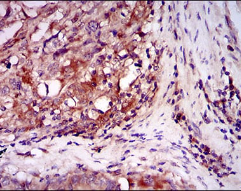

IHC    1/200 - 1/1000